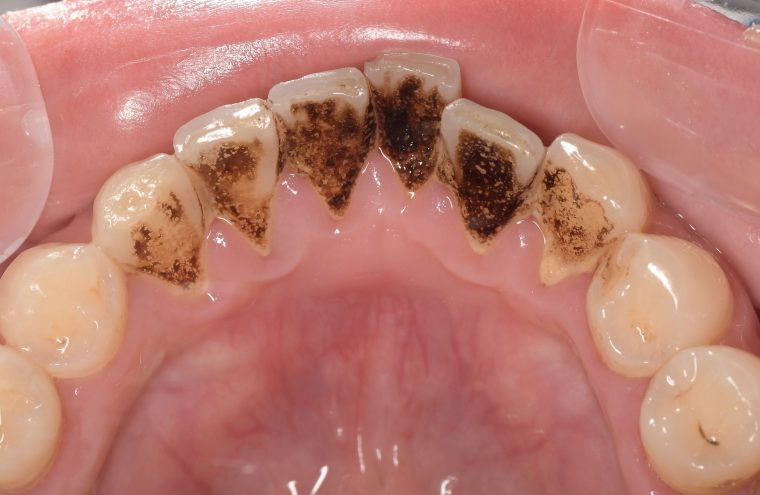

CASE 10

Before①

After①

Before②

After②

基本情報

| 年齢・性別 | 38歳・男性 |

|---|---|

| 主訴 | 下顎 歯石除去したい |

| 治療内容 | スケーリング |

| 治療期間 | 30分 |

| 治療費 | 約1,500円(保険診療) |

| リスク・副作用 | 知覚過敏、歯肉退縮 |

| 治療方針 | 歯肉縁上歯石を除去してから歯肉縁下歯石を除去します。ご自身でのプラークコントロールができるようになったら定期検診に移行します。 |

| 担当者所見 | 半年ぶりの歯科医院の受診。歯石が付きやすいためセルフケアの重要性をお伝えして、定期的にクリーニングを行います。出血率が高く炎症が強いため、今後はセルフケアを強化して歯周病治療を行います。 |